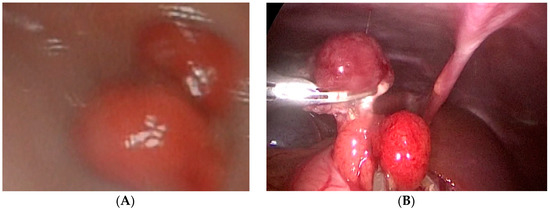

Our third case is a 2-year-old child who was admitted to hospital due to blood and mucus in the stool. Intraoperative colonoscopy revealed polypoid form diameter around 2 cm, 30 cm from the anocutaneous line that showed ulcerations and was on the wide base. Biopsies were sent for pathohistological examination. The endoscopic histologic diagnosis was a polyp of the sigma and chronic colitis. A polypectomy was performed using a laparoscopic–endoscopic “rendezvous” procedure. Infraumbilical open access with the 5-millimeter Hasson technique was used to create pneumoperitoneum. The working ports were placed in epigastric and in the upper right quadrant. By lighting from the lumen of the colon, an enterotomy was performed (Figure 1A). The polyp was visualized, resected in its base (Figure 1B), and sent for definitive pathohistological examination. A direct enterorrhaphy during the laparoscopy was performed in the standardized manner. The operation was completed, and the postoperative period was uneventful.

Figure 1. (A) Endoscopic guidance from the lumen of the intestine and a place of enterotomy, (B) Complete visualization of the polyp and its resection.